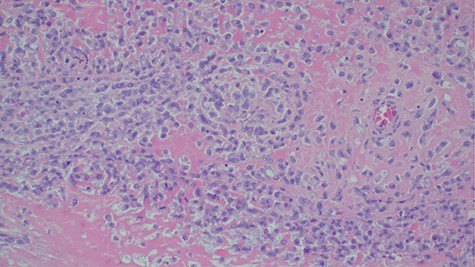

Laboratory investigations revealed a low platelet level of 53 per microliter and hemoglobin level of 10.7 g/dl. Renal profile, white blood count and serum electrolytes were within normal range. Computed tomography intravenous urogram revealed a large heterogeneous mass, measuring 5.5 × 4.5 cm at the right superolateral aspect of the urinary bladder with ipsilateral hydronephrosis and hydroureter. Bone scan study was unremarkable. Urothelial cell carcinoma of the urinary bladder was clinically suggested as the most likely differential diagnosis. Cystoscopy was done under spinal anesthesia, which revealed a solid mass with areas of necrosis at the anterior bladder wall. The biopsy was taken whose histological evaluation revealed a high-grade malignant mesenchymal tumor made up of oval or spindle cells with osteoid formation in many areas of the lesion (Fig. 1). No definite carcinomatous component was appreciated. The tumor was strongly positive for vimentin immunohistochemistry staining (Fig. 2) and negative for cytokeratin 20. Calcified schistosomal ova were also seen (Fig. 3).

Calcified schistosomal ova near or within the tumor (H&E ×400).

A number of risk factors for primary extraskeletal osteosarcoma have been reported in the literature. Radiotherapy, schistosomal infection, trauma, diverticulitis, use of chemotherapy agents such as cyclophosphamide and frequent urinary tract infections have been implicated [1, 6]. Our patient had schistosomiasis (Fig. 3) which might have been the predisposing risk factor.